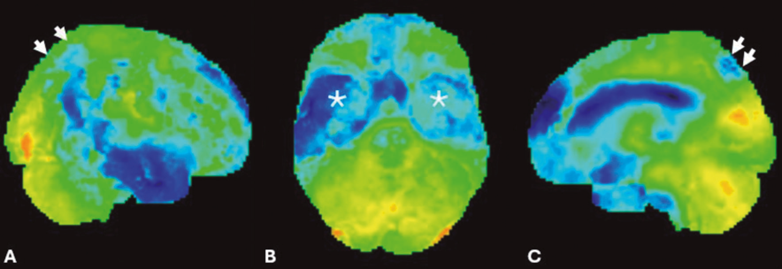

Um estudo complementar com tomografia por emissão de pósitrons (PET-CT) com fluordesoxiglicose (FDG) demonstrou hipometabolismo bilateral e simétrico dos pré-cúneos e dos giros dos cíngulos posteriormente, assim como dos lobos temporais e parietais, poupando as regiões sensitivo-motoras primárias (figura 2). Por fim, um estudo de PET-CT com 18F-Florbetabeno demonstrou a deposição cortical de placa beta amiloide evidenciando captação cortical do radiofármaco de ambos os hemisférios cerebrais (figura 3).

Figura 2. Imagens de PET-CT 18F-FDG com reconstruções 3D e quantificação voxel a voxel com software Scenium® com visão lateral direita (A), inferior (B) e parassagital esquerda (C) demonstram hipometabolismo bilateral e simétrico dos pré-cúneos (setas em C), assim como das regiões mediais dos lobos temporais (asteriscos em B), e a convexidade parietal bilateral (setas em A) poupando as regiões sensitivo-motoras.